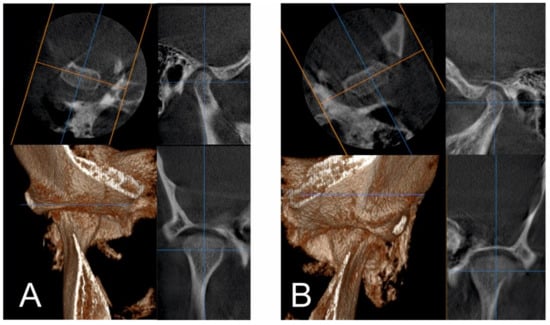

2.1. Initial Diagnosis and Initial Surgical Management

3. Results